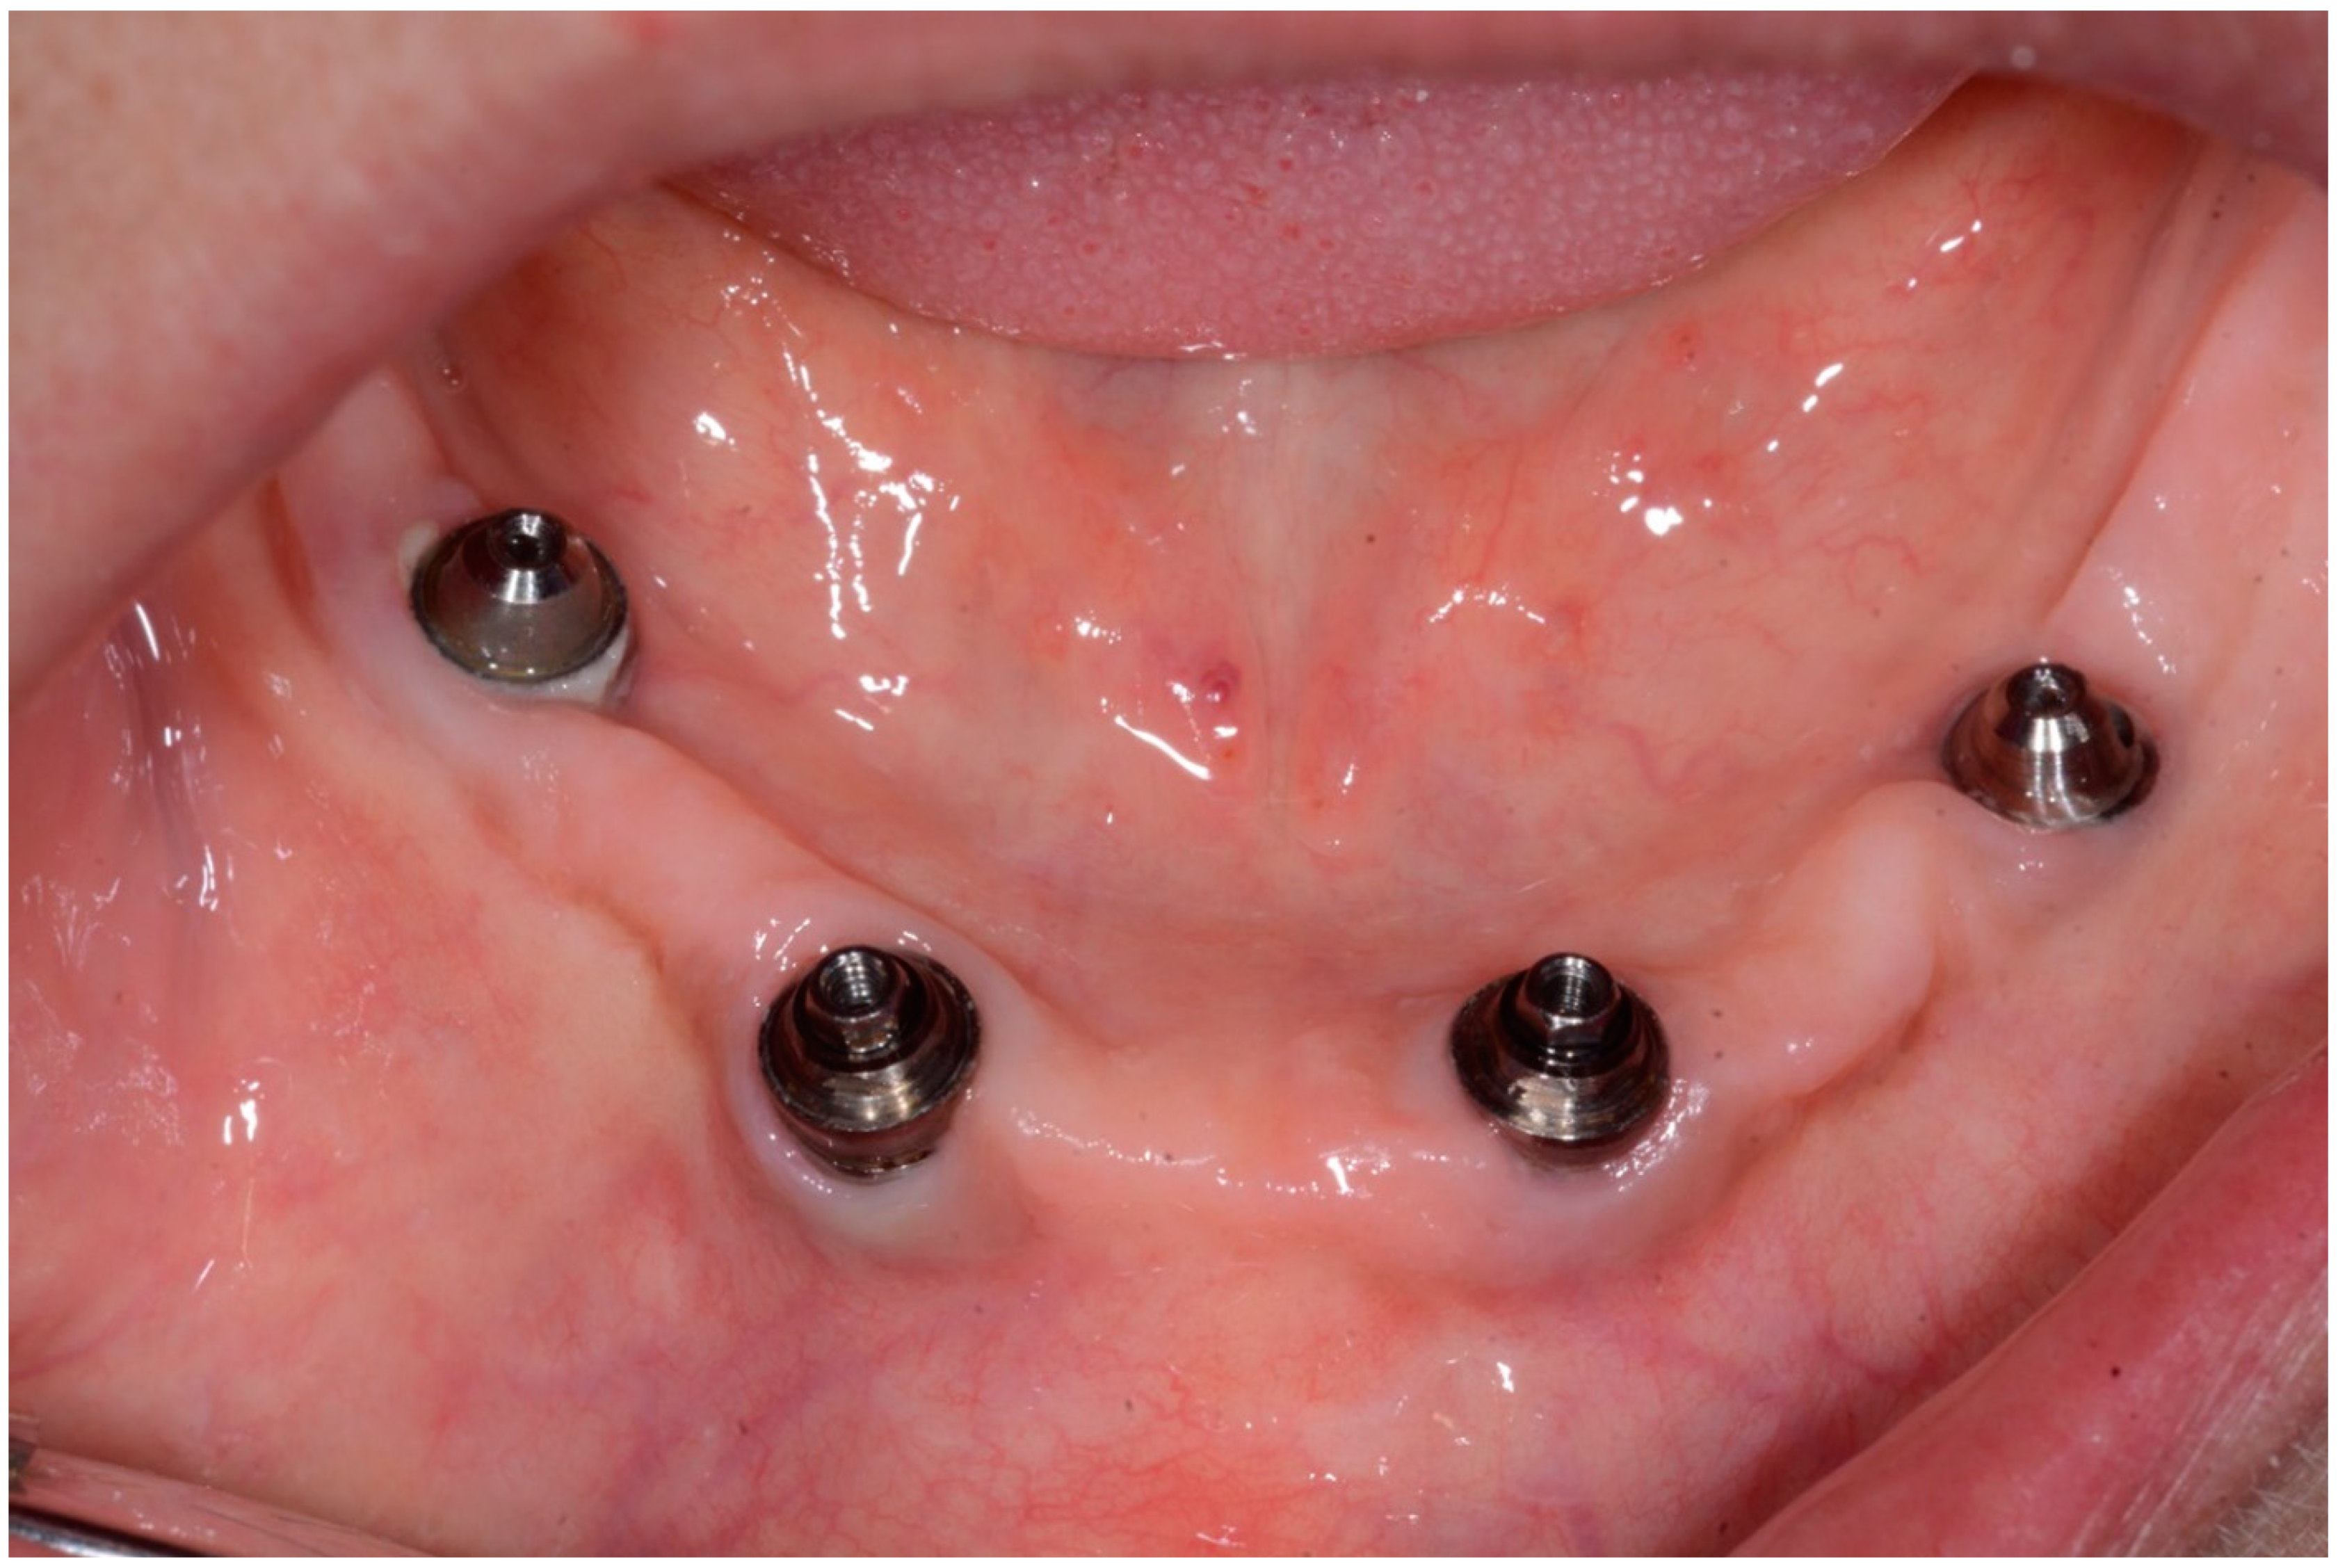

2.2. Case Report 2